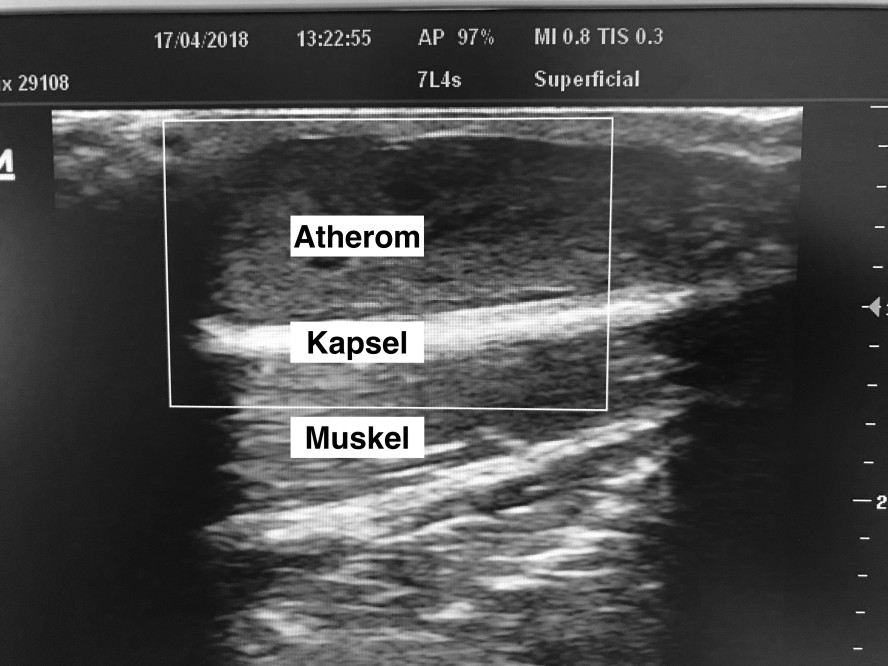

Hinter diesen Begriffen verbirgt sich ein Talgknoten, der in der Haut und im Fettgewebe unter der Haut liegt. Atherome treten am Kopfes, dort vor allem in den Haaren, aber auch im Gesicht auf. Atherome am behaarten Kopf nennt man Grützbeutel. Nicht selten finden sich Atherome auch am Rücken oder am Bauch. Wenn Atherome am Hodensack auftreten, nennt man sie Skrotalzysten.

Neben jedem Haar befindet sich eine Talgdrüsen, die das Haar fettet. Wenn der Ausführungsgang der Talgdrüsen verstopft ist, kann der Talg nicht abfließen. Dann sammelt sich der Talg in der Talgdrüsen und dehnt diese aus. Durch die fortlaufende Talgproduktion schwillt die Talgdrüse immer weiter an und kann schließlich getastet werden. So kann aus einer mikroskopischen Struktur ein viele Zentimeter großer praller elastischer Knoten in der Haut entstehen.